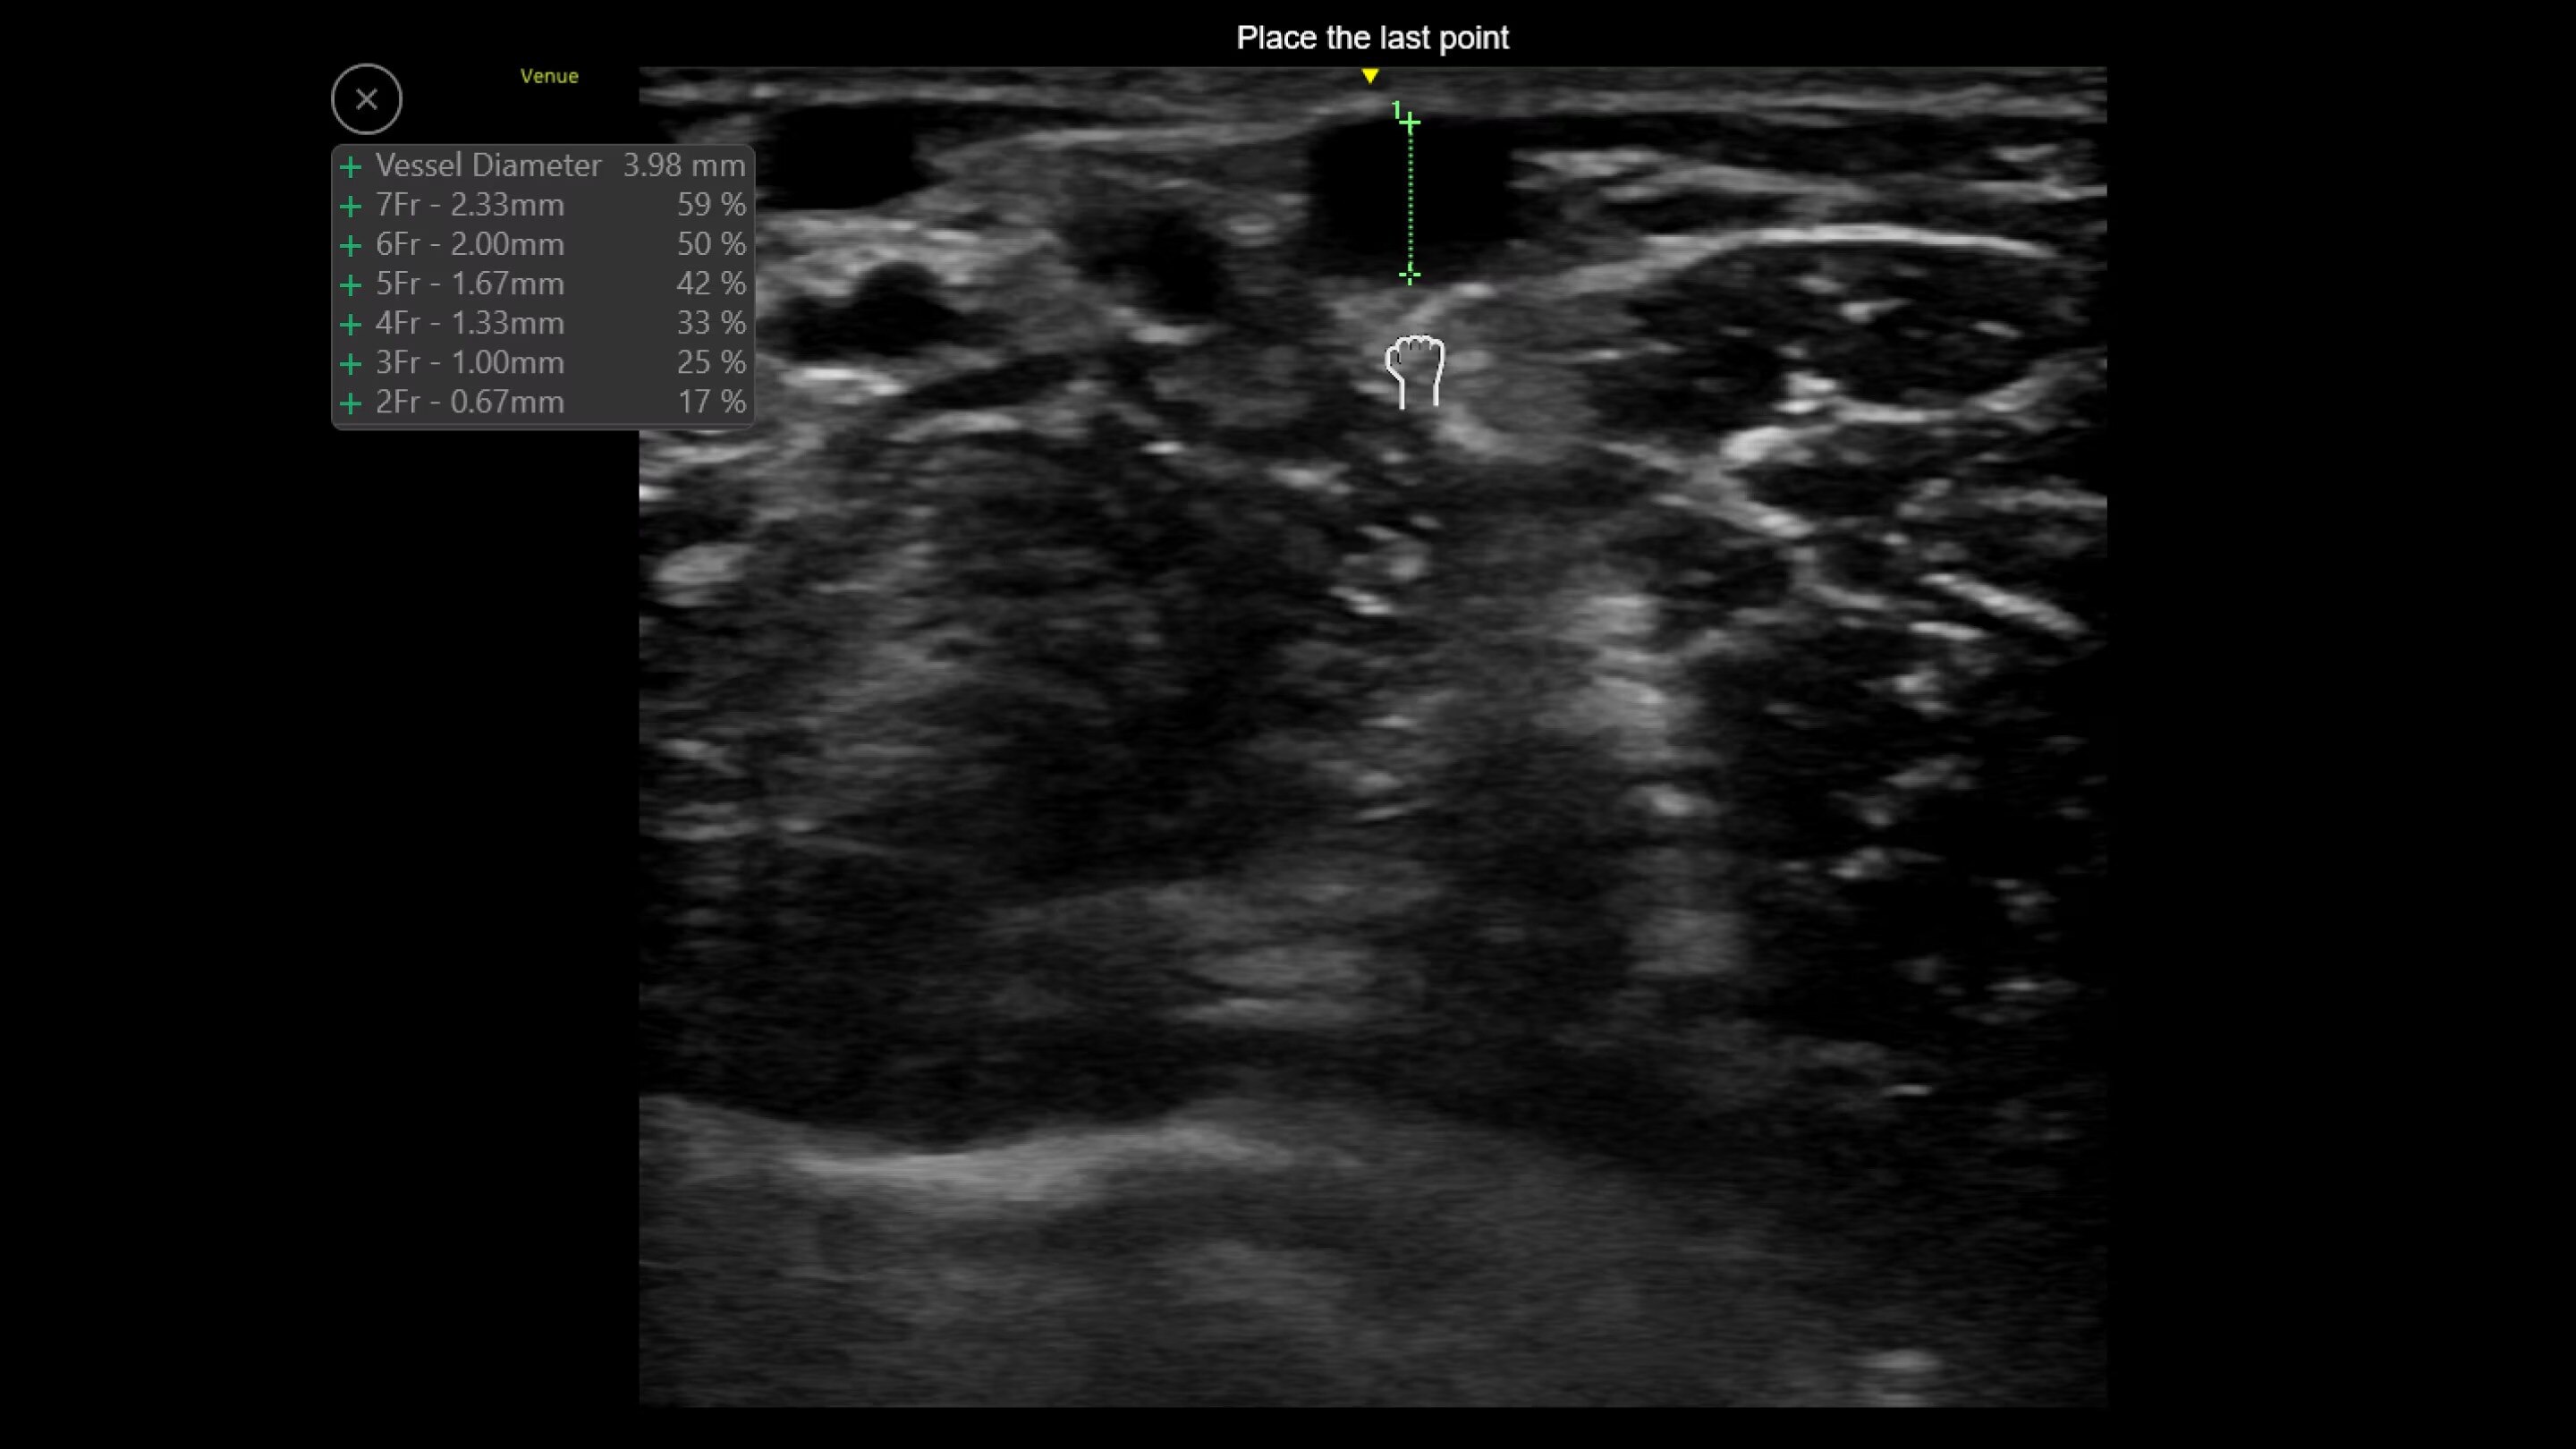

Nerveblox™

Perform ultrasound-guided peripheral nerve blocks with Nerveblox

Standard for Venue and Venue Go this AI-enabled tool automatically labels key anatomical landmarks in the ultrasound image, helping clinicians feel confident during the procedure and streamlining the workflow with the goal of reducing procedure time.